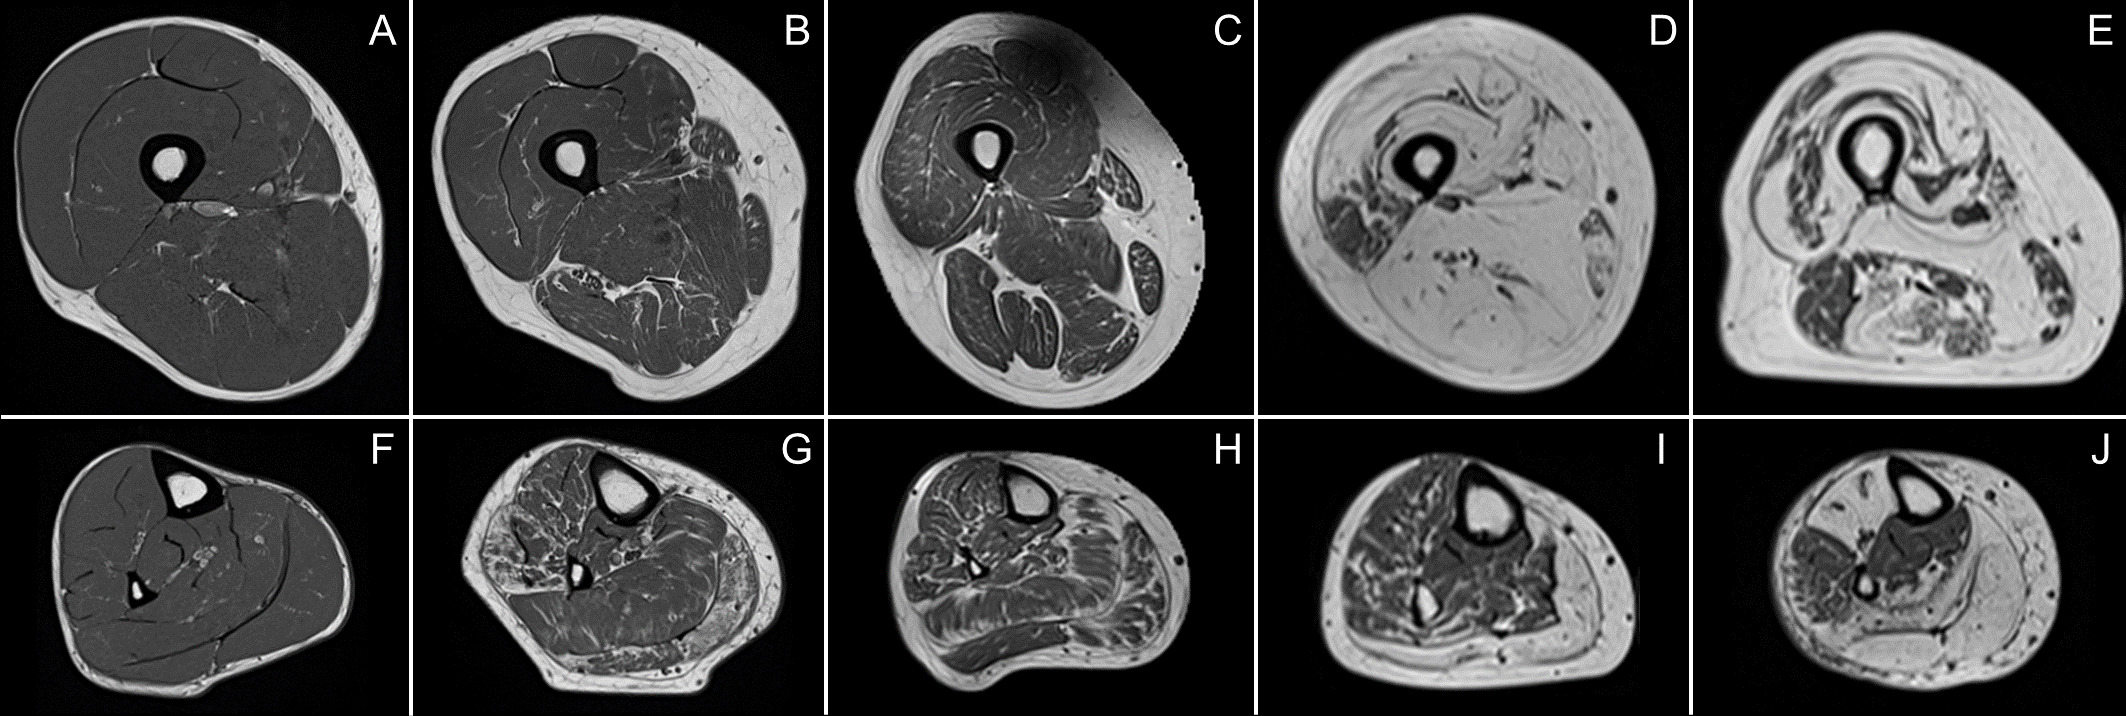

Examples of T1-weighted images of thighs (first row) and lower legs (second row) of a healthy subject (A,F) and patients with Charcot–Marie–Tooth disease type 1A (B,G), myotonic dystrophy type 1 (C,H), facioscapulohumeral muscular dystrophy (D,I), and inclusion body myositis (E,J).